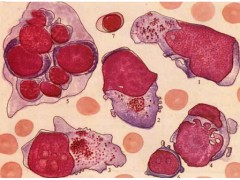

宫颈癌,HeLa

【规    格】1株/1ML

【储存条件】低温保存

【产品商标】ATCC

【供应限制】仅供科研使用